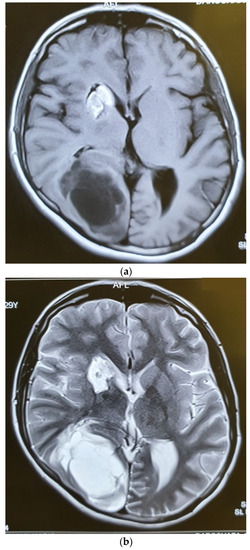

Six months after radiotherapy, the MRI showed a very good response to the treatment, with no mass lesion and non-specific enhancement at C2 and C3 (Figure 5). The thoracic and lumbar MRI and the thoracic and abdominopelvic contrast-enhanced CT scans were all normal. Three months later, she developed headaches and visual complaints. The MRI depicted a large right parietooccipital lesion with ring enhancement in favor of metastasis (Figure 6). We suggested surgery and radiation for the brain lesion and chemotherapy, but the patient refused any other treatment and therefore was a candidate for supportive care.

Figure 6.

Axial T1W (a), T2W (b), and Gad-Enhanced MRI (c) showing the large cystic mass in the right parietooccipital area together with the old lesion in basal ganglia.